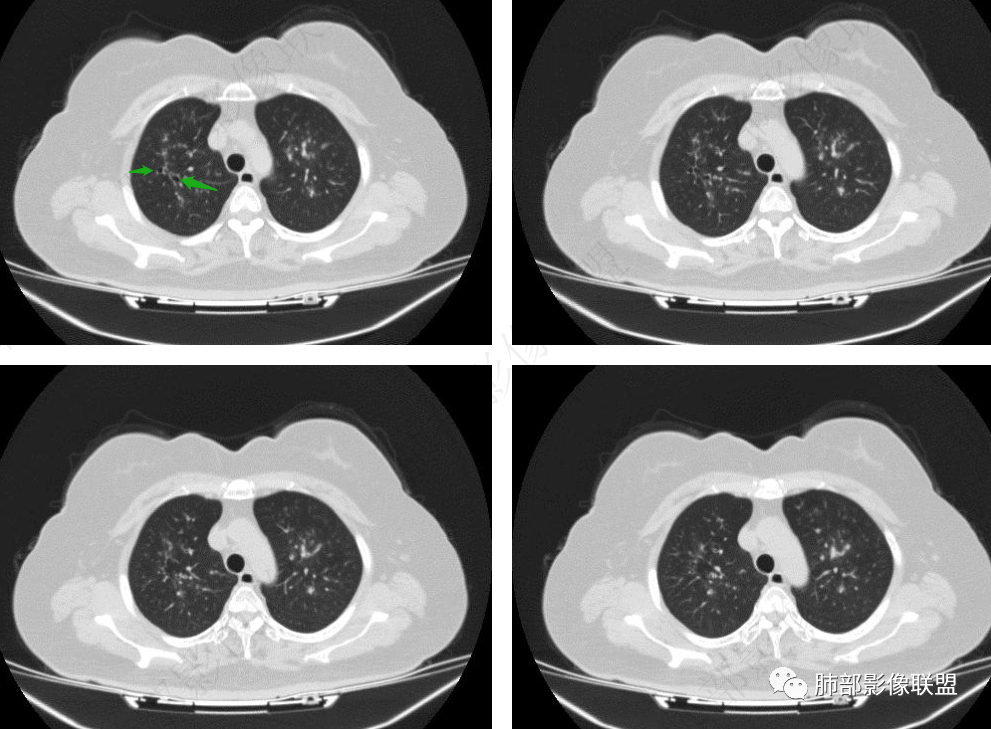

老年女性,发现白细胞升高两年,此次入院多次查外周血白细胞>30*10^9/L,淋巴降低,CRP显著升高,但病程中无发热,以细菌性炎不好解释;CT提示有脾大,结合外周血象,首先考虑存在血液系统疾病(白血病)基础,且未系统诊治;肺部CT提示双肺中轴间质增粗,伴随支气管管壁增厚?多发树丫及腺泡结节,部分呈点晕征,可见肺动脉分枝增粗,一元论考虑白血病肺部浸润;二院论考虑白血病并发气道侵袭曲霉。以患者病程进展看,更倾向于白血病肺部浸润。

1.病灶沿支气管分布的特点相当明显,相应支气管壁广泛增厚。这种与支气管关系极为密切的片影和/或结节影,常高度提示气道相关感染,如支气管肺炎。

2.患者两肺多发病变,具有广泛性。如此广泛分布更多见于免疫低下的机会性感染。

3.支气管壁广泛增厚对气道侵袭性曲霉病具有一定的提示意义。注意患者没有支气管扩张,临床也未提供IGE等实验室资料。

1.器官支气管管套样壁增厚和/或支气管扩张,注意壁增厚较均匀,和/或伴有播散性小片影及结节影,注意这些小片影或结节影边界有时较普通炎性病灶清楚。

四.变应性支气管肺曲霉病(ABPA)

1.三四级以上支气管显著扩张,柱状扩张为主,常伴痰液嵌塞,远端支气管相对正常,强烈提示ABPA诊断!ABPA的支扩有时来得快去得快。

影像上表现为V形、Y形、葡萄状或指套状阴影,边缘清楚。

2.管腔扩张及管壁增厚(炎性反映),轨道征或环形影常比较显著;

3.病变远端的肺组织可有肺不张表现,或因侧支通气而出现过度充气征象。

另可有渗出性肺泡炎改变:肺实质内单发或多发斑片状密度增高影,上叶多见,可为一过性、游走性或持续较长时间。